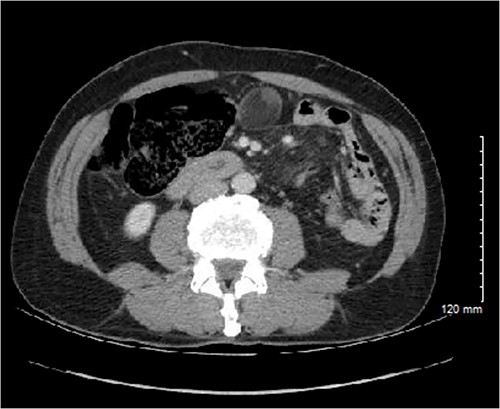

The patient underwent serial cross-sectional imaging that demonstrated stable appearance of the mass with migration of the redundant cecum and associated mass into the pelvis (Fig. 2). Colonoscopy showed a normal cecal base and no concerning features apart from sigmoid colon polyps. Due to the location, percutaneous biopsy was considered but ultimately was non-feasible due to anatomic constraints.

CT imaging from 4 months after initial diagnosis, showing a 4.0 × 3.6 × 3.8 cm, seemingly lipomatous mass in the midpelvis.